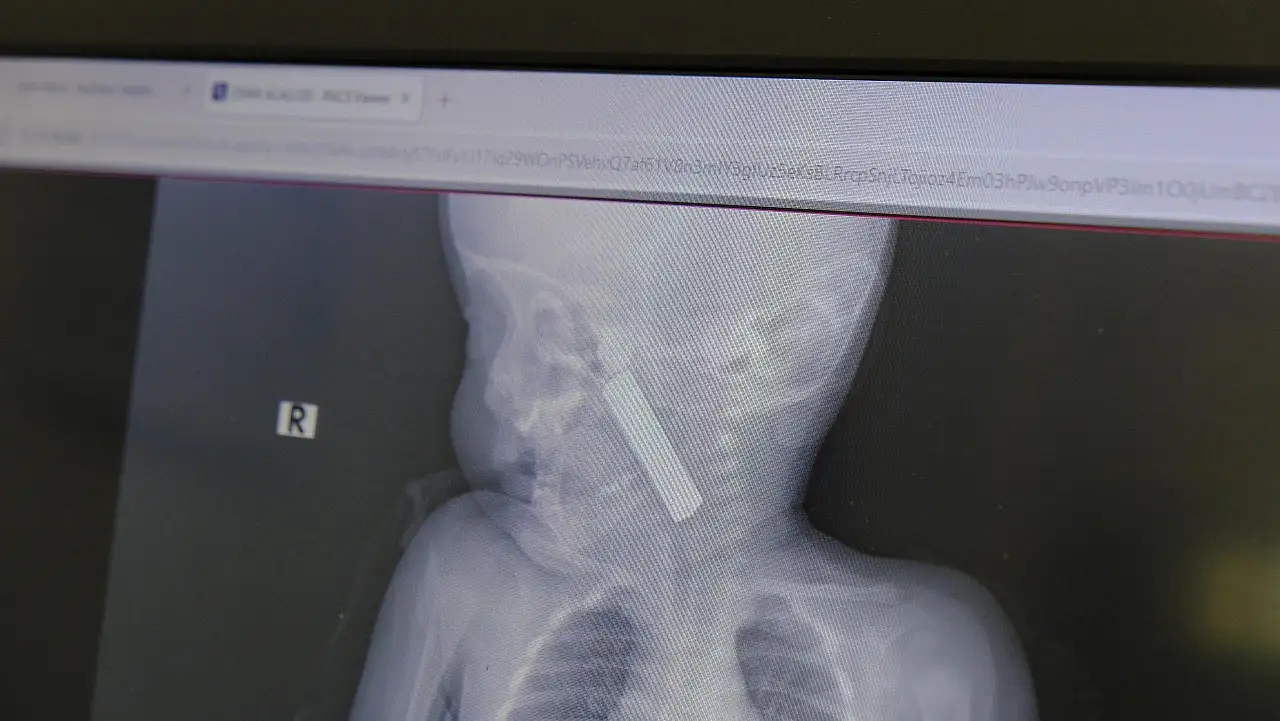

İhlas Haber Ajansı'nda (İHA) yer alan haberdeki iddiaya göre; kusma şikayeti ile ailesi tarafından Karaman Eğitim ve Araştırma Hastanesi acil servisine getirilen 6 aylık E.A. isimli kız bebeğin, yapılan muayene ve tetkiklerde boğazında kumanda pili kaçtığı tespit edildi. Solunum sıkıntısı da yaşayan bebek hemen ameliyata alındı.

Çocuk Cerrahisi Uzmanı Doç. Dr. Mehmet Uysal tarafından yapılan ameliyatla bebeğin boğazındaki pil çıkarıldı.

Yaşanan olayla ilgili bilgi veren Doç. Dr. Mehmet Uysal, "Acil polikliniğimize kusma şikayeti ile 6 aylık bir kız bebek getirilmiş ve bize haber verildi. Biz de vakit kaybetmeden geldik, hastamızı gördük. Yapılan tetkikler sonucunda, ağız tabanına oturan ve yemek borusunun birinci darlığına kadar uzanan, kumanda pili dediğimiz bir pille karşılaştık. Filmde ve muayenede bunu gördük. Hastayı ilk gördüğümüzde bayağı siyanotik durumda, solunum sıkıntılıydı ve oksijen satürasyonu 90 civarındaydı. Böyle olunca bir an önce beklemeden hızlı bir şekilde ameliyathaneye götürdük. Orada ameliyathanedeki anestezi uzmanlarımız ve personel bize yardımcı oldu, hasta hızlı bir şekilde entübe edildi. Ondan sonra da laringoskop ve magill forseps dediğimiz malzemelerimizle bu yabancı cismi çıkarmış olduk. Bir an evvel müdahale ettik, iyi ki müdahale ettik, orada ağız tabanında, özellikle ön kısmında hasar oluşmuştu. Müdahale sonrasında da hastanın solunum problemleri bir süre devam etti, bu yüzden 24 saat takip ettik. Herhangi bir problem oluşmayınca 24 saat sonra kontrole gelmek üzere hastayı taburcu ettik" diye konuştu.